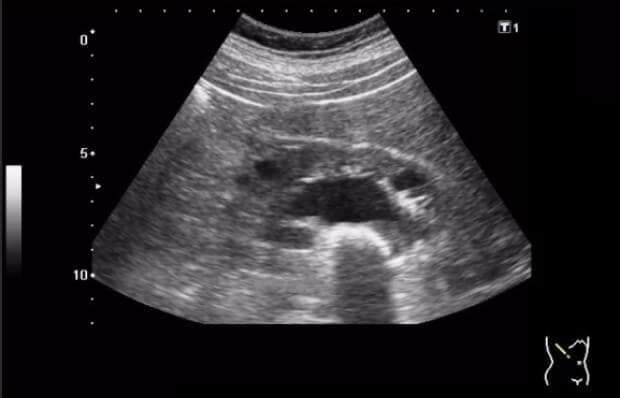

Za mjesec dana ultrazvuk je pokazao da se cista duplo smanjila - sa 20 mm je spala na 10 mm! A dva od tri kamena su se istopila i izašla (sjećam se da me boljelo prilikom mokrenja par dana prije ovoga). Onda sam prešla na običnu dozu. Za mjesec dana, doktor je bio u šoku kad je uradio ultrazvuk - bubrezi su bili čisti!